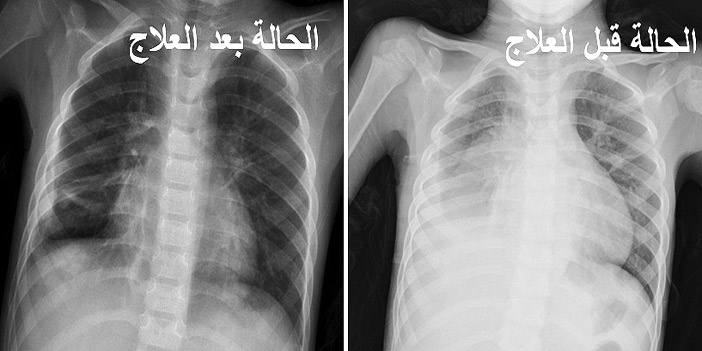

استشاريون علاج الالتهاب الرئوي يختلف وفقا لدرجة الإصابة وطبيعتها صحيفة الاقتصادية

فريق طبي بجامعة الملك خالد ينجح في علاج لالتهاب رئوي لطفل